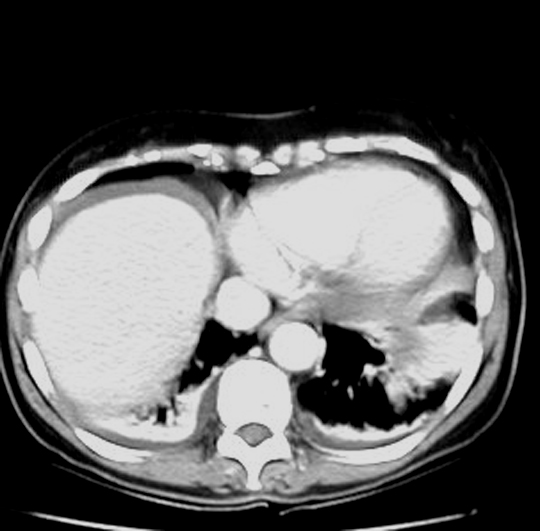

CT: Highly accurate

Signs: